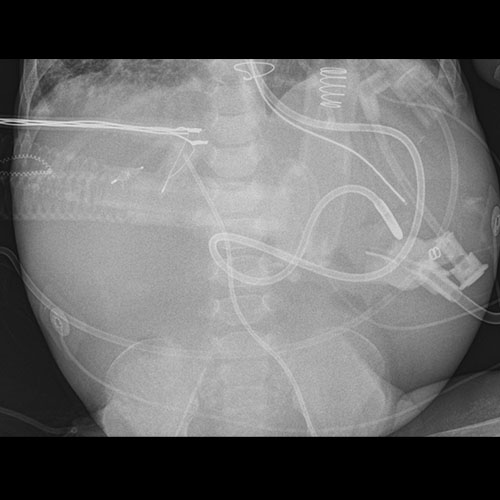

There are additional lines, tubes, catheters, or drains in place. (e.g. chest tubes, mediastinal drains, rectal temp probe, etc.)

There is dilatation with gas or fluid of multiple or diffuse loops of bowel.

​Both the small and large bowel are filled with air and/or fluid and may or may not be distended.

There is an NG/OG/FT tube which is malpositioned.